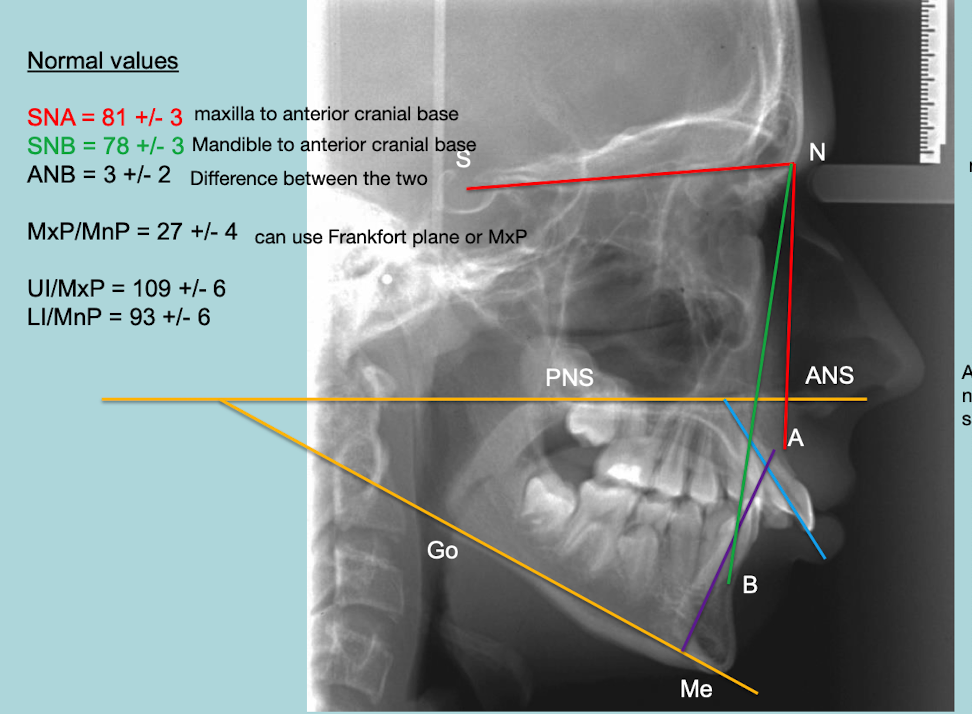

What are normal ceph values

not class2, normal

• SNA= 81+/-3 (maxilla to anteiror cranial base)

• SNB= 78+/-3 (mandible to anterior cranial base)

• ANB= 3 +/-2 (difference between the two)

• MxP/MnP= 27 +/-4

• UI/MxP = 109+/-6

• LI/MnP = 93 +/-6

• LAFH/TAFH = 55%